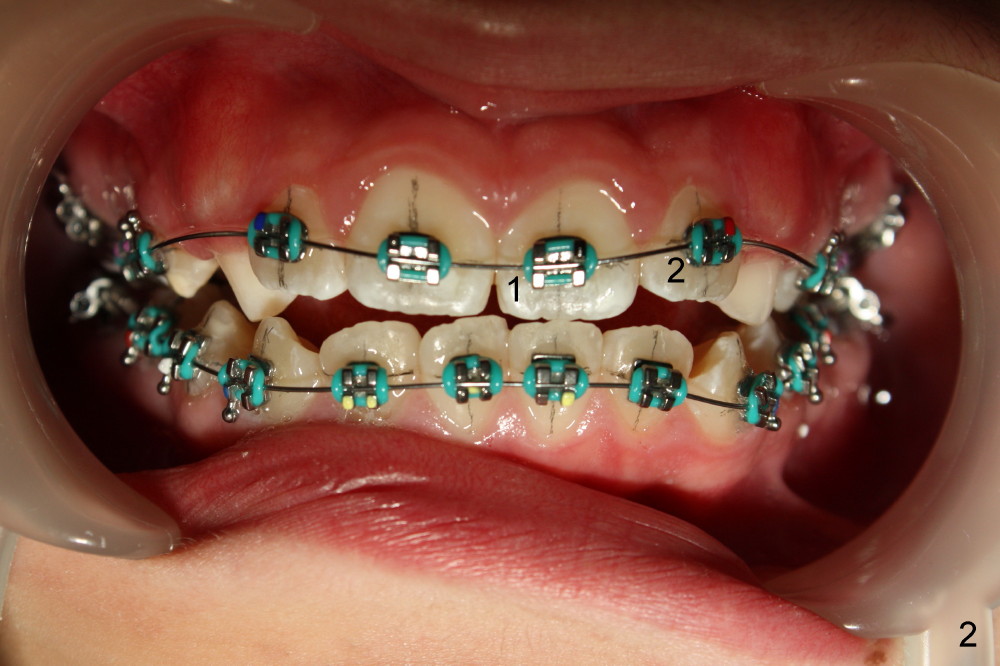

4. Upper 2nd bicuspids (u5s) rotate (Fig.4, 5). Use power chains (Fig.6 different case) to correct rotation quickly to use E space to facilitate u3s eruption (Visit 2)

5. Use rotation wedge for u1s or lower one(s) if necessary (Fig.7, 8; Visit 2)